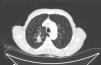

Two punch biopsies and a new blood test were taken, including serum protein levels, viral serologies, blood smear, muscle enzymes, Sézary cells, flow cytometry, and immunological and tumoral markers. The remainder of the laboratory findings were within normal limits (including serum aldolase) except of Creatin phosphokinase (CPK) (1.309IU/L; normal range 1–175IU/L) and creatine kinase-MB (CK-MB) (27.3IU/L; normal range 0–20IU/L). Histological specimens revealed mild spongiotic and psoriasiform changes with discrete follicular hyperkeratosis, as well as nonspecific histopathology features (Fig. 4). We started a supportive treatment with emphasis on hyperproteic diet; temperature and hydration control in addition to topical steroids. Because of the new-onset of weight loss and concern for underlying malignancy as a potential cause for his erythroderma, a thorough workup for occult malignancy was completed. A chest computed tomography revealed 22×34mm nodular lesion on the upper right lobe with multiple lymphadenopathies (Fig. 5), being the histopathology compatible with a squamous cell carcinoma. Head computed tomography demonstrated two occipital metastatic lesions, being finally classified as IV stage (T2N3M1). At 6 weeks, the patient's rash was similar to that at the initial presentation, however less itchy. The patient died after 3 months of the diagnosis due to metastatic cancer progression.